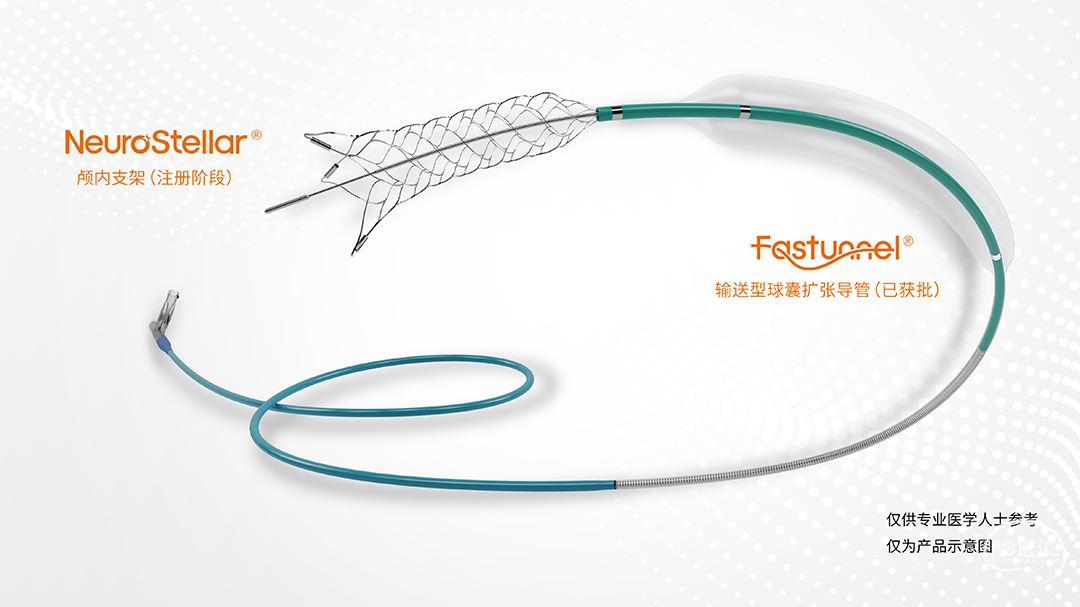

术中涉及介入器械选择

· 加奇生物 21系列 Fastunnel®输送型球囊扩张导管 2.0*15mm

· 自膨式闭环支架 3.0*21mm

使用“零交换”技术沿21系列 Fastunnel®输送型球囊扩张导管 2.0*15mm上行自膨式闭环支架 3.0*21mm,到位后顺利释放。

“零交换”技术,充分减少了手术步骤,降低手术风险(步骤越多,风险越大)。